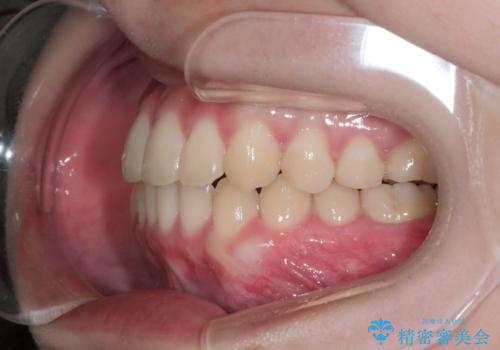

八重歯とクロスバイト:インビザライン治療

- 八重歯が気になるとの事でご相談にいらした方です。

インビザラインで綺麗に並べました。

気になっていた八重歯が綺麗になって大変喜んでいただけました。